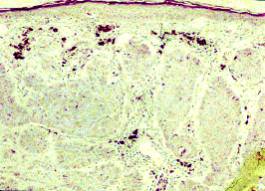

CARCTERISTICAS HISTOPATOLOGICAS

Se reconocen varios tipos histológicos de Carcinoma de Células Básales pero en general la enfermedad se caracteriza a nivel microscópico por la presencia de patrones circunscritos o difusos con una proliferación de células epiteliales basaloides que presentan un expectro de patrones de crecimiento que oscila de sólido a adenoideo quístico. En el patrón histológico circunscrito surgen nidos y cuerdas de células cuboidales de la región de las células Básales Epidérmicas, en el patrón difuso se encuentran nidos infiltrativos pequeños en un estroma fibroblástico.

La célula basal es una célula pluripotencial que puede desarrollarse en varias direcciones y formar pelo, glándulas sebáceas y glándulas sudorípadas o Epitelio escamoso y por último queratina. Otro rasgo frecuentemente observado en el estroma del Carcinoma de Células Básales es un aumento del contenido de tejido elástico. 1,5,6,7

Con todos estos exámenes realizados al paciente se procedió para la toma de la muestra la cual consistió en una biopsia excisional bajo sedación intravenosa. Una vez obtenida la muestra la cual se denomina Biopsia Extemporánea o por congelación ya que se envía al laboratorio anatomopatológico de inmediato, el resultado final o diagnóstico histopatológico fue EPITELIOMA BASOCELULAR NODULAR FOCALMENTE ULCERADO, con moderada reacción desmoplástica y leve respuesta inflamatoria. Los márgenes de recesión laterales y profundos, amplios, totalmente libres de lesión por lo cual el paso siguiente consistió en el cierre quirúrgico del defecto causado por la toma de la muestra.

Estudio Histopatológico.